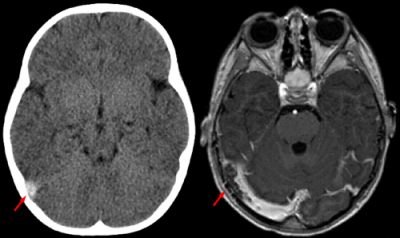

Risonanza magnetica: immagini di output

Questo esame fa pur sempre parte della radiologia, in quanto genera immagini relative alla struttura interna del corpo umano, ma fornisce elementi di natura diversa, infatti l'RMN, mette in evidenza solo i tessuti molli, facendo una netta distinzione tra le diverse tipologie, dando un risultato finale, difficilmente ottenibile con le altre forme di radiologia. Essa è in grado di produrre immagini di tipo tomografico digitale, utilizzando campi magnetici e radiofrequenze, si può definire una tecnica multiparametrica e multiplanare, che permette di ottenere sezioni di organi e vario orientamento su piani sagittali, dorsali o trasversali, con assenza di artefatti, dovuti alle strutture ossee e soprattutto senza alcun bisogno di spostare il paziente.